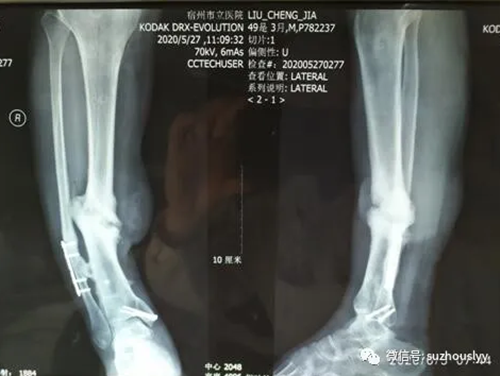

患者男性、40多岁,2年前因车祸致左侧小腿骨折,在外院给予手术治疗,术后出现切口感染,皮肤坏死,再次手术给予清创及皮瓣转移修复术,术后皮瓣边缘愈合不良,再次给予自体骨髓干细胞移植,术后骨折端仍然愈合较差,多次治疗费用花掉家里所有的积蓄,精神上受到巨大的打击给家庭和生活带来困难。

慕名前来我院就诊,骨三科主任杨峰接诊后,对该患者前病史进行研判,由于患者多次手术致局部条件较差,再次手术困难极大,综合考虑到畸形矫正后血管的痉挛,转移皮瓣的血供,腓骨截骨的方式以及胫骨骨不连内固定的方式,制定了手术方案及术后可能出现并发症的预防措施,经过团队的共同努力和麻醉科的配合下截骨矫形术非常成功,术后患者恢复较好,病情顺利康复!